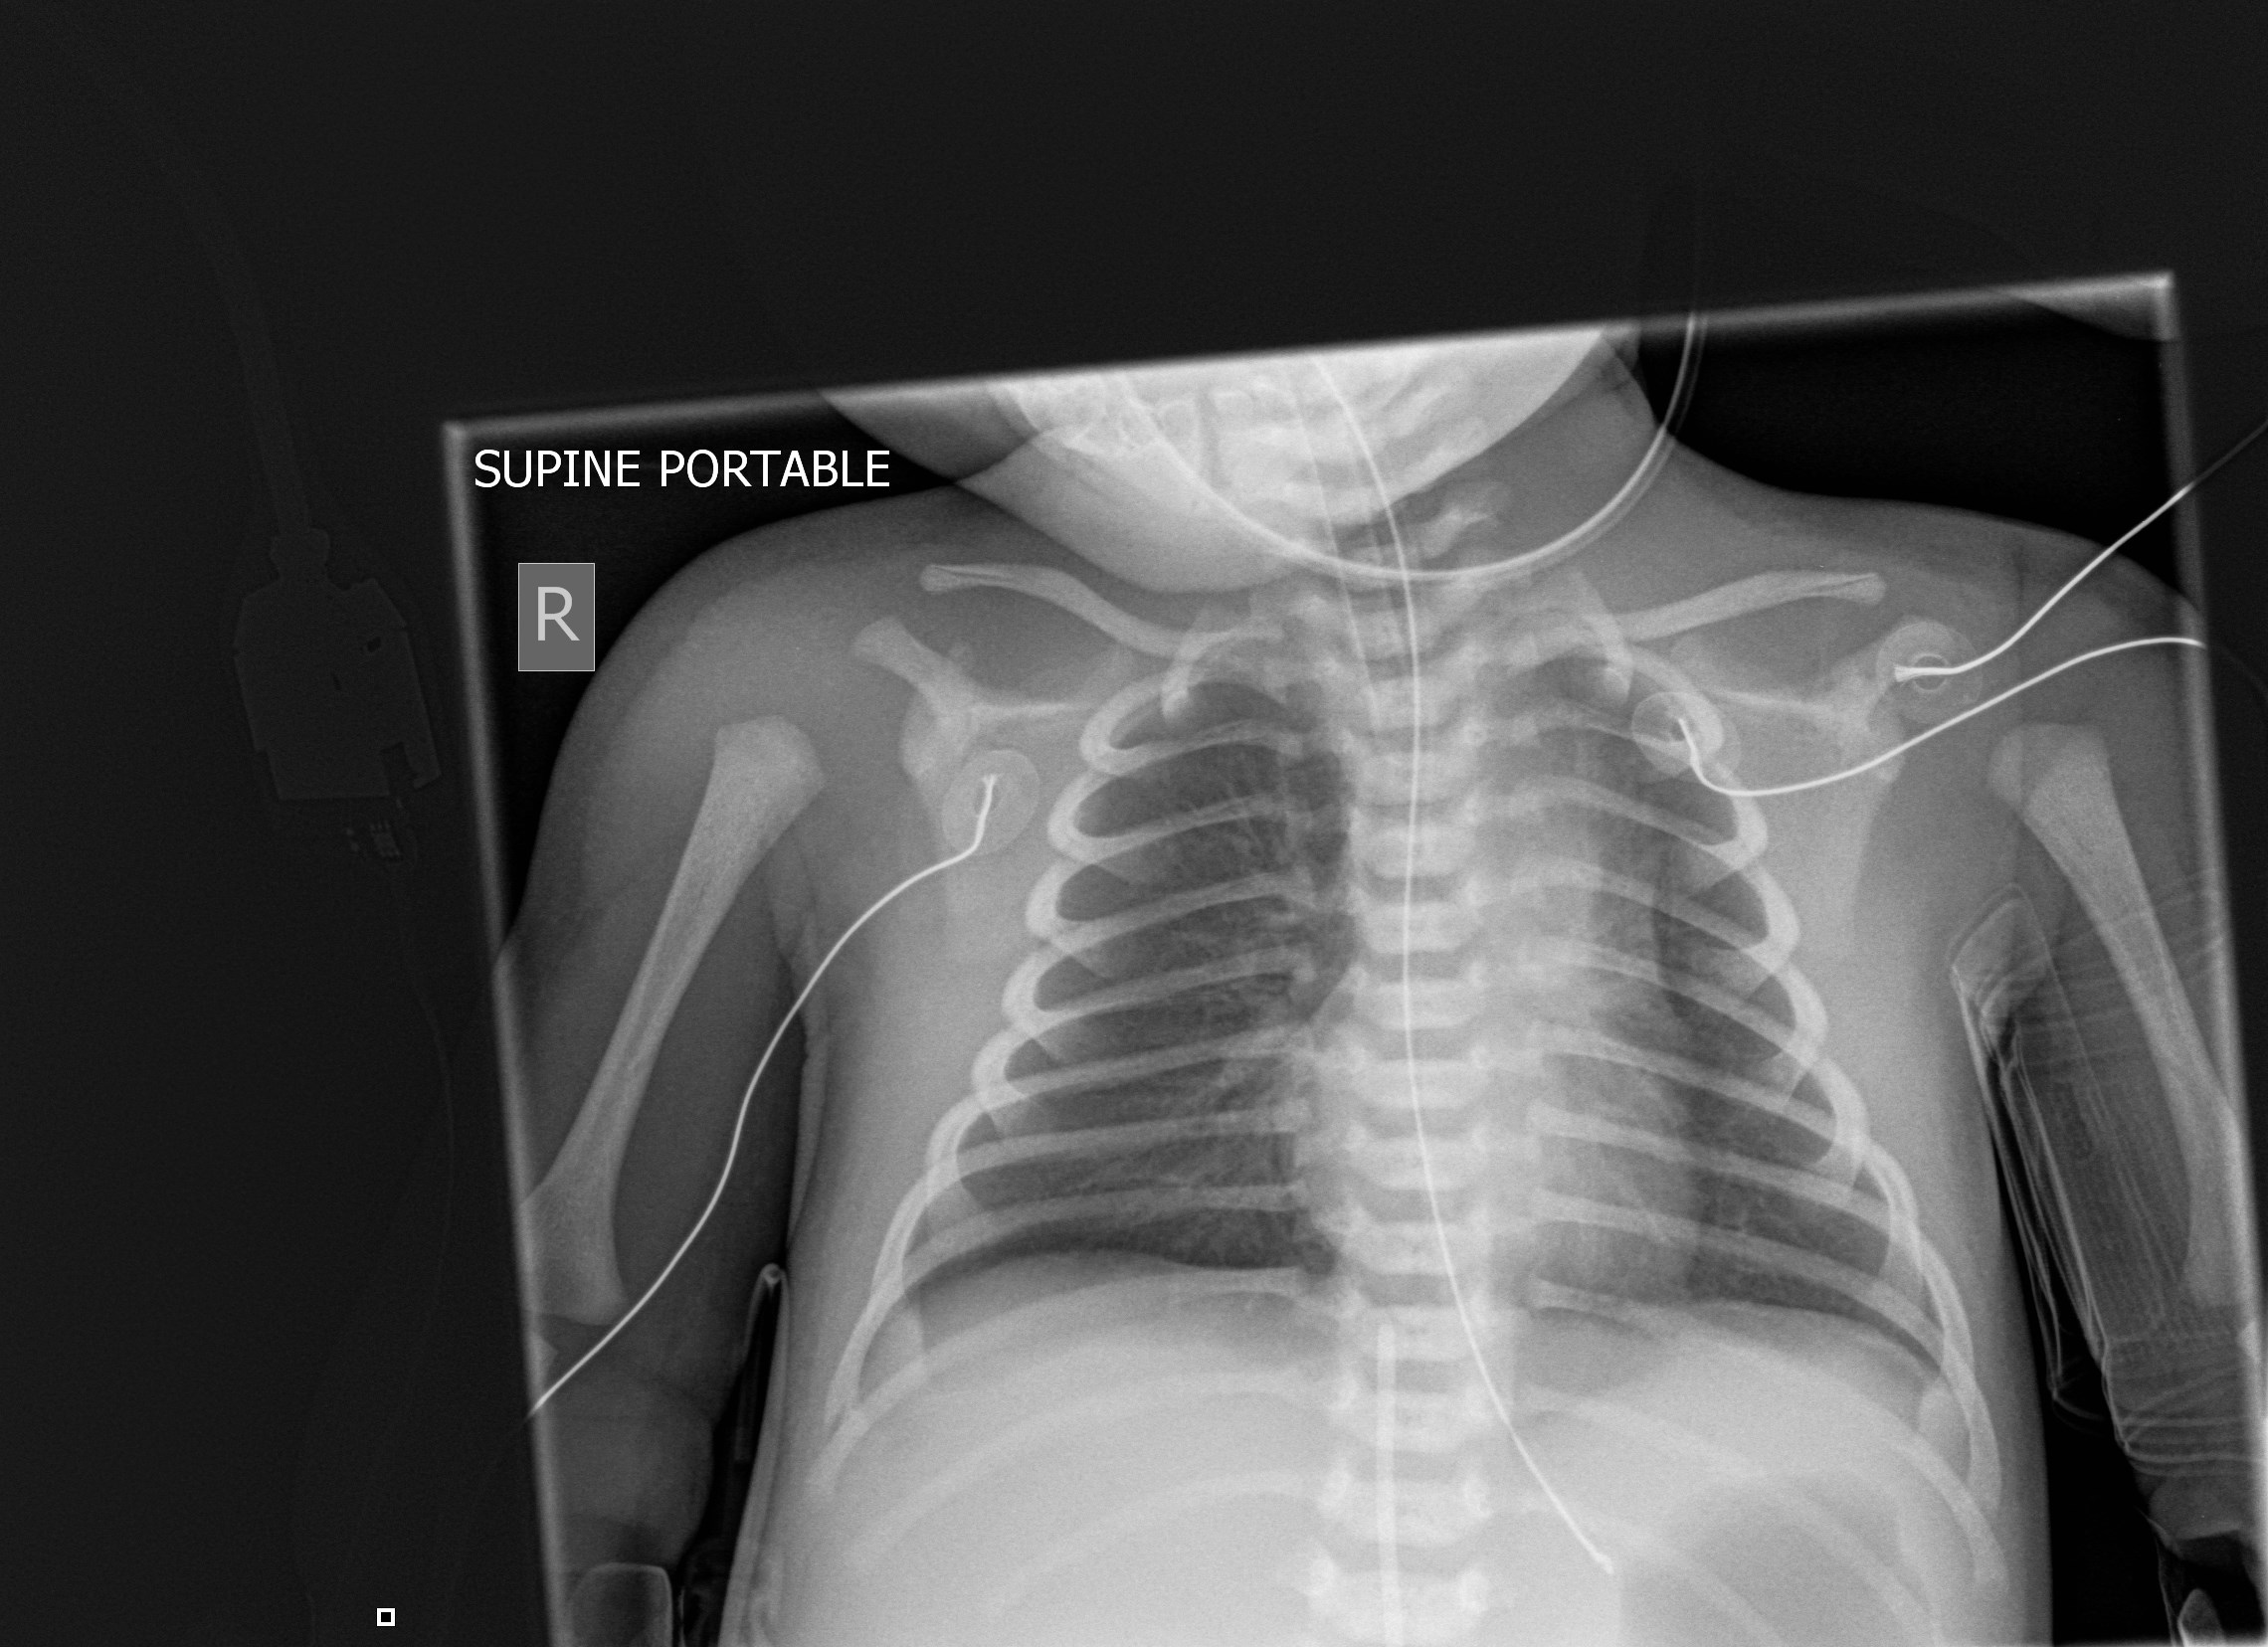

Normal Chest X Ray Of Newborn . The thymus is prominent but rapidly involutes during the first. The normal shape of the chest in the newborn is trapezoid with horizontal ribs. A specific finding on neonatal chest films is air leak tracking along the bronchi termed pulmonary interstitial emphysema (pie). This article lists examples of normal imaging of the pediatric patients divided by region, modality, and age. The specific reason why these radiographs are. Standard chest radiograph is an anteroposterior projection. Basics of interpreting a neonatal chest radiograph. Air within the interstitium can cause stiff and. Normally, thymus appears as a bilateral smoothly. One needs to differentiate its normal from abnormal appearance. The anteroposterior (ap) diameter of the neonatal chest is almost as great as its transverse.

One needs to differentiate its normal from abnormal appearance. Normally, thymus appears as a bilateral smoothly. The thymus is prominent but rapidly involutes during the first. The specific reason why these radiographs are. Basics of interpreting a neonatal chest radiograph. Air within the interstitium can cause stiff and. The normal shape of the chest in the newborn is trapezoid with horizontal ribs. A specific finding on neonatal chest films is air leak tracking along the bronchi termed pulmonary interstitial emphysema (pie). This article lists examples of normal imaging of the pediatric patients divided by region, modality, and age. The anteroposterior (ap) diameter of the neonatal chest is almost as great as its transverse.